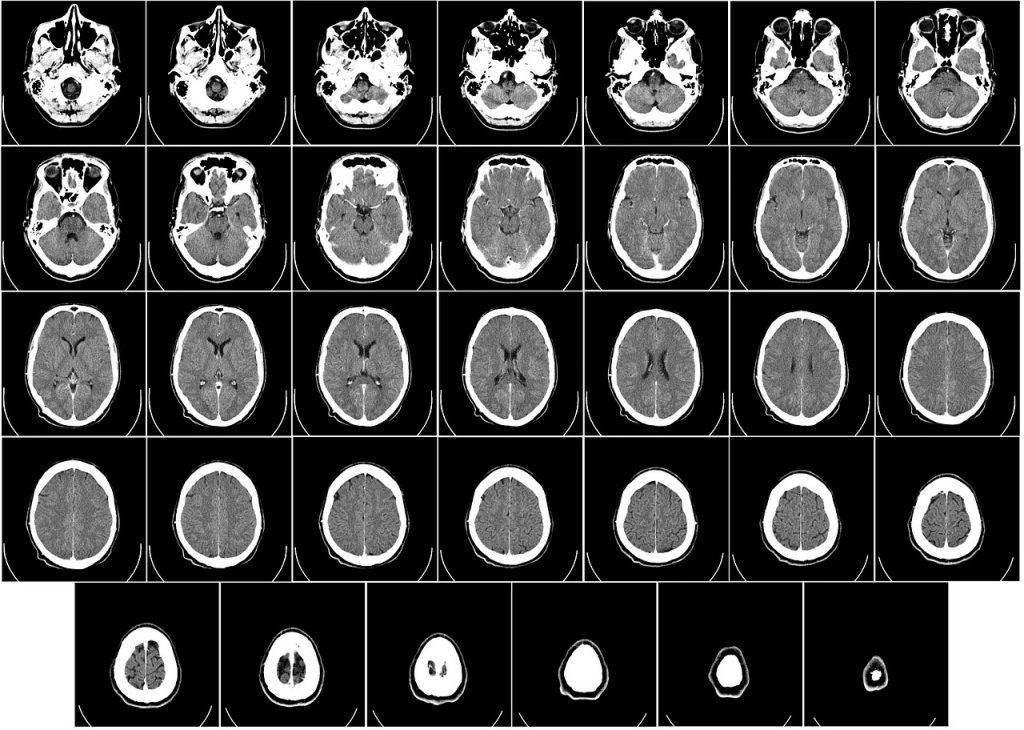

Brain PET CT

Brain studies using FDG is done for accurate evaluation of dementia based on reduced glucose metabolism in specific areas is brain which is generally normal structurally as visualized by MRI studies. Brain PET is useful in chronic epilepsy patients as modality to identify seizure focus amenable for surgical ablation.